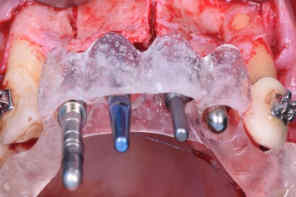

Three vertical osteotomies were performed in the buccal cortical bone up to the medullary portion, at the mesial of the

canines and midline (Figure 6), followed by alveolar ridge crest osteotomy between the canines (Figure 7). All osteotomies were performed under abundant irrigation with saline solution. Subsequently, the surgical guide was tested, observing the positioning of each implant (Figure 8).

Figure 8: Testing of Surgical Guide.